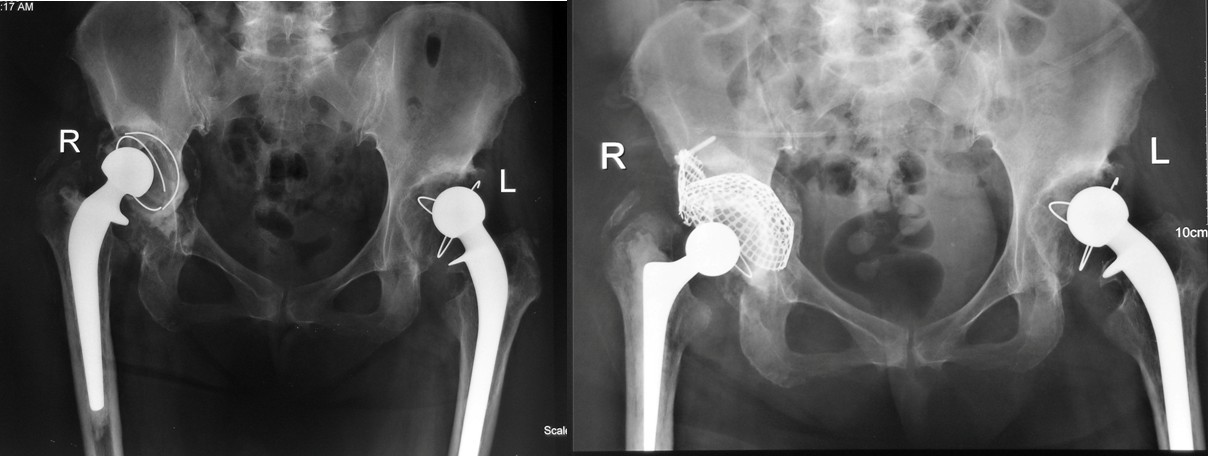

在对髋臼存在骨缺损的病例进行手术前计划时,首先要判断这一缺损是包容性还是非包容性骨缺损,对于包容性骨缺损可以直接采用植骨、打压,而对于非包容性骨缺损,要借助金属网(wire mesh)将非包容性骨缺损转化为包容性骨缺损,继而进行植骨、打压。最为准确的分型是在手术中,对髋臼进行充分显露后完成的。打压植骨技术的基本目标是通过强有力的打压获得坚固的骨重建,对髋臼的重建必须达到:髋臼完整性的完全恢复;骨或金属网对臼杯的完全覆盖;移植骨被完全的限制住并牢固的固定;假体的牢固固定以及髋关节正常机械功能的重建。

手术于超净层流手术室内完成,采用前外侧Hardinge入路,充分显露髋臼后对骨缺损类型与程度进行评价。用金属网将非包容性骨缺损转化为包含性骨缺损,逐层填入直径约8-10mm的异体松质骨颗粒,以专用打压器进行强有力的打压,直至将骨缺损完全充实,运用第三代骨水泥技术,选择标准大小髋臼杯,真空搅拌抗生素骨水泥,持续加压将骨水泥渗透入骨小梁中,达到内锁机制,放置髋臼杯于解剖位置。

颗粒骨打压植骨技术使用金属网包容骨缺损,使非包容性骨缺损转为包容性骨缺损,金属网的优势是可塑性高,与骨床贴附紧密并可以根据术中缺损的实际情况进行随意裁剪。同时采用新鲜冷冻松质骨填充缺损,用专用器械进行强有力的打压,使骨颗粒填充密实牢固,提高了骨愈合的能力与机会。